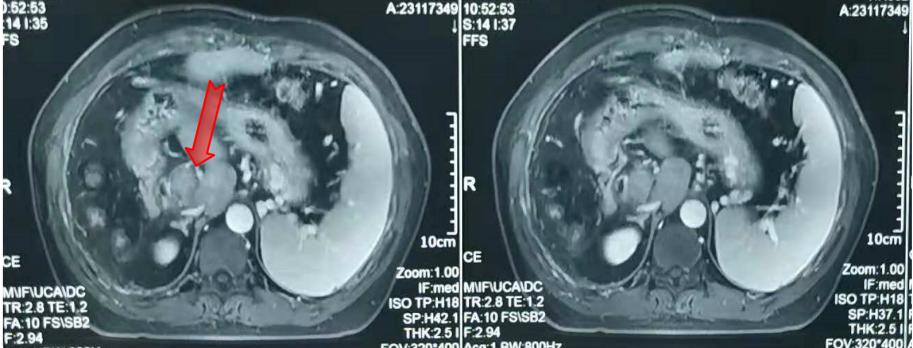

随后患者定期复查,并开始口服仑伐替尼治疗。因乏力、纳差等不良反应,患者服药2月后拒绝继续服用,停药观察。AFP持续升高。2017年底患者开始服用瑞戈非尼治疗。AFP出现短暂下降,2018年2月初AFP再次反弹。复查MR提示左叶可疑病灶(图6)。

图6. 靶向治疗后腹部MR

2018年1月开始在瑞戈非尼基础上加用纳武利尤单抗100 mg q2w。AFP出现短暂降低后继续上升,2018年3月到达整个治疗过程的最高值65.8 ng/ml,随后AFP出现断崖式下降,1个半月后降到正常范围。使用纳武利尤单抗2个月后复查MR,提示DWI无明显高信号,可能为放疗联合免疫治疗导致的肝损伤(图7)。2018年6月至今AFP波动在0.86 ng/ml~1.90 ng/ml之间。治疗全程AFP变化情况见图8。

图7. 免疫治疗2个月后腹部MR